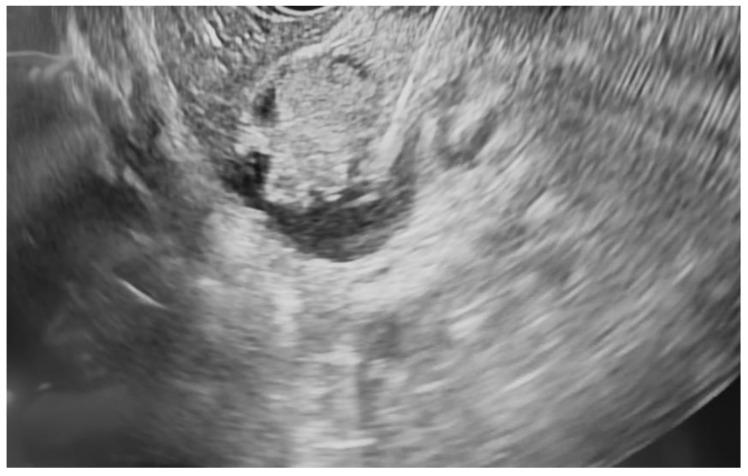

Pancreatic neoplasms, including adenocarcinoma, pancreatic neuroendocrine tumors (pNETs), intraductal papillary mucinous neoplasms (IPMNs), and high-grade cystic lesions, often require surgical resection as a form of curative treatment. However, comorbidities and high-risk features may preclude surgery. Endoscopic ultrasound-guided radiofrequency ablation (EUS-RFA) has emerged as a minimally invasive alternative with proven cytoreductive efficacy in solid tumors. This case series evaluates the safety and efficacy of EUS-RFA in patients with various unresectable, non-metastatic pancreatic neoplasms. A retrospective review was conducted on eight patients who underwent EUS-RFA at our institutions between July 2021 and February 2025. All patients were deemed unsuitable surgical candidates due to comorbidities such as advanced age, cardiovascular disease, renal insufficiency, and COPD or due to patient resistance to surgical intervention. EUS-RFA was performed using a 19-gauge RFA needle (Taewoong Corporation). Follow-up imaging was conducted 3 to 6 months after the completion of RFA treatment. All eight patients demonstrated a good to excellent response in terms of tumor size reduction. The most notable response was observed in a patient with pNET, resulting in complete resolution from 15.6 × 12.0 mm to 0.0 × 0.0 mm after two RFA treatments. Other neoplasms, including pancreatic adenocarcinoma and intraductal papillary mucinous neoplasms (IPMNs), also demonstrated significant reductions. Mild post-procedure complications, including pancreatitis and abdominal pain, were noted in three cases. EUS-RFA is a promising alternative for managing unresectable pancreatic neoplasms in high-risk patients. Our findings support its use across various tumor types with favorable outcomes and minimal complications, reinforcing its role in expanding therapeutic options beyond surgery.

胰腺肿瘤,包括腺癌、胰腺神经内分泌肿瘤(pNETs)、导管内乳头状黏液性肿瘤(IPMNs)和高级别囊性病变,通常需要手术切除作为一种根治性治疗方式。然而,合并症和高风险特征可能使手术无法进行。内镜超声引导下射频消融术(EUS-RFA)已成为一种微创替代方法,在实体肿瘤中具有已被证实的减瘤疗效。本病例系列评估了EUS-RFA在各种无法切除的非转移性胰腺肿瘤患者中的安全性和有效性。对2021年7月至2025年2月期间在我们机构接受EUS-RFA治疗的8例患者进行了回顾性研究。所有患者均因高龄、心血管疾病、肾功能不全和慢性阻塞性肺疾病等合并症或患者对手术干预的抗拒而被认为不适合手术。使用19号射频消融针(太永公司)进行EUS-RFA。在射频消融治疗完成后3至6个月进行随访成像。所有8例患者在肿瘤缩小方面均表现出良好至优异的反应。在1例pNET患者中观察到最显著的反应,经过两次射频消融治疗后,肿瘤从15.6×12.0毫米完全消退至0.0×0.0毫米。其他肿瘤,包括胰腺腺癌和导管内乳头状黏液性肿瘤(IPMNs),也表现出显著缩小。3例患者出现了轻度术后并发症,包括胰腺炎和腹痛。EUS-RFA是管理高危患者无法切除的胰腺肿瘤的一种有前景的替代方法。我们的研究结果支持其在各种肿瘤类型中的应用,具有良好的疗效和最小的并发症,强化了其在扩展手术以外治疗选择方面的作用。